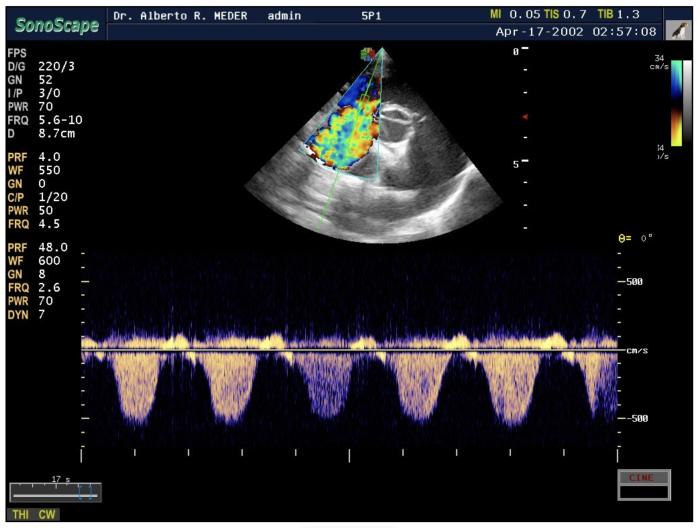

No constituye una prueba diagnóstica definitiva, ya que para este fin se requiere cateterismo cardíaco derecho, sin embargo, el uso de la ecocardiografía Doppler para estimar la presión arterial pulmonar es crucial en la evaluación ecocardiográfica de perros con sospecha de HP12. El Doppler espectral continuo del tracto de entrada del ventrículo derecho, utilizado como estimación indirecta de la presión arterial pulmonar sistólica, muestra una velocidad pico de regurgitación tricuspídea >3.4 m/s (>46 mmHg)2en casos graves (la presión arterial pulmonar sistólica puede subestimarse en presencia de hipertensión grave en la aurícula derecha) (Figura4).